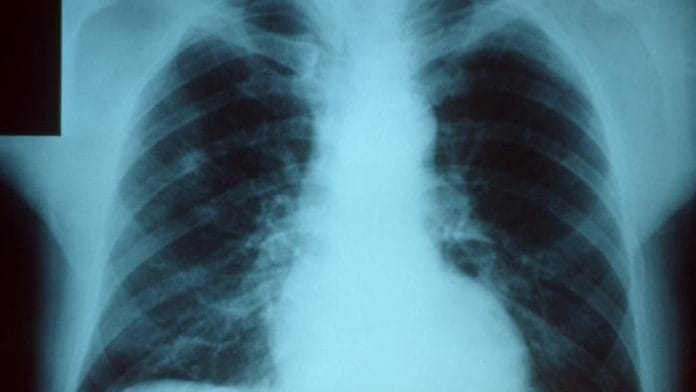

Pneumonia is caused by bacteria, viruses or fungi, and leaves children fighting for breath as their lungs fill with pus and fluid.